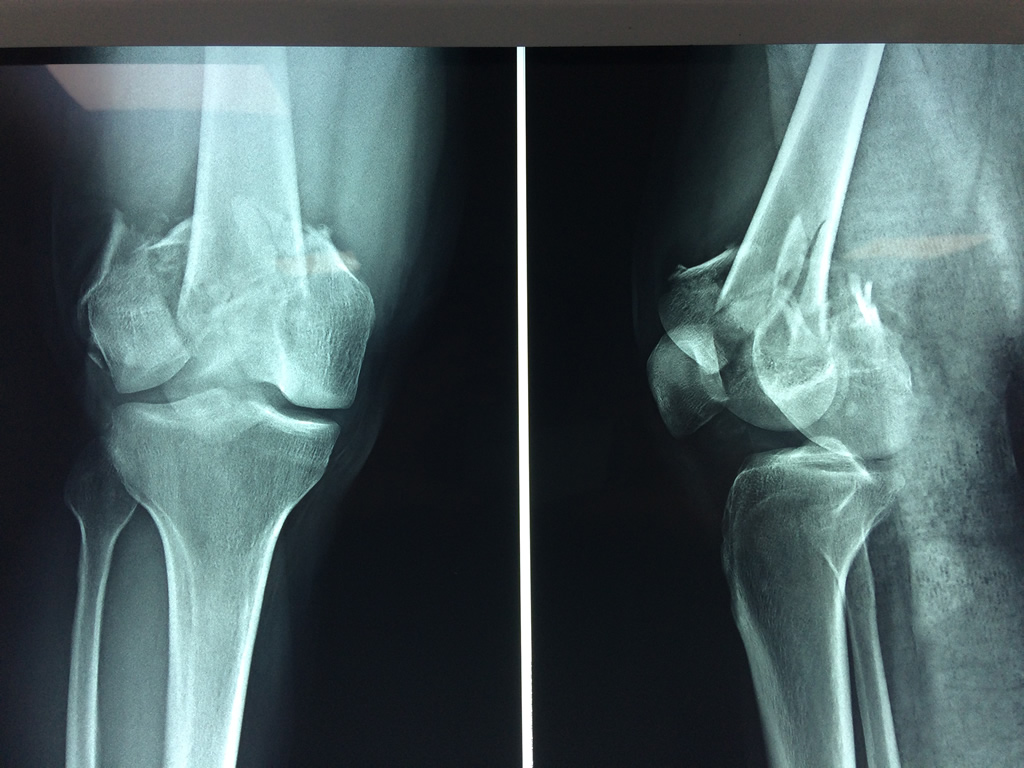

Cirugías de Húmero - Fémur

El fémur es el hueso del muslo, el segundo segmento del miembro inferior. Es el hueso más largo, fuerte y voluminoso del cuerpo humano.